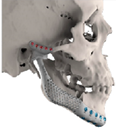

| 4 | 71 | FA-M3 | ![]() | Left zygomatic arch, glenoid fossa and complete left hemimandible extended to the right hemimandible ramus | Alloyed titanium zygomatic backing capping the UHMWPE fossa | Titantium alloy | Skull component: 82.3 mm titanium screws. Manibular component: 62.7 mm titanium screws |